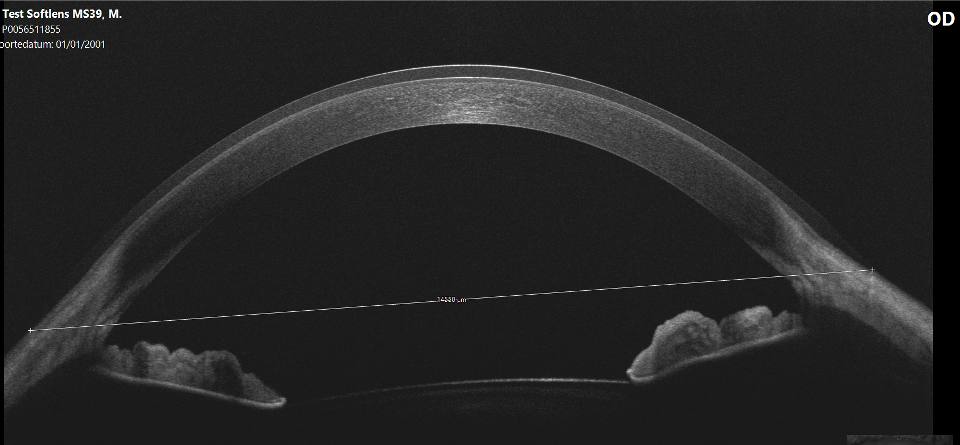

As part of the ongoing soft lens fitting project at Pacific, we decided to replicate this study and to add another variable: a variety of base curves. Eight different lathe-cut lenses of known base curve and sagittal height (measured at eye-temperature, 34 °C) and a labelled diameter of 14.5 were manufactured by Mark’ennovy in Spain (Saphir, silicone hydrogel, Filcon 5B, 75% water content, Dk 60, modulus 0.13 MPa). They were placed on a standard (average) eye, and the on-eye diameter increase was measured using anterior segment OCT (Visante, Zeiss/Germany).

What is really intriguing is that the 7.7 mm base curve lens had an on-eye diameter increase of almost 1 mm (0.97 mm to be exact). One base curve flatter (8.0 mm) had an on-eye diameter increase of 0.77 mm; for the 8.3 mm base curve this was 0.53 mm, and for the 8.6 mm base curve a 0.27 mm increase was measured. For reference, the relative sagittal heights of these lenses were 680, 480, 248, and 46 microns (for the 7.7 mm, 8.0 mm, 8.3 mm, and 8.6 mm base curves, respectively).

Switching to flatter base curves of 8.9 mm, 9.2 mm, 9.5 mm, and 9.8 mm did not change anything; the diameter did not increase more than with the previous 8.6 mm base curve lens (the numbers were respectively 0.27 mm, 0.23 mm, 0.26 mm, and 0.23 mm increase). It’s important to note that the delta-SAGs of these four lenses were -143, -380, -520, and -650, respectively (note that these are negative values, so they varied from a little bit flatter to excessively flatter than the ocular surface).

The bottom line overall is that there was a steady decline in on-eye diameter gain from 7.7 mm to 8.3 mm base curves in roughly 0.20 mm steps for each base curve until a tipping point was reached at which the lens and ocular surface were on-par with each other, after which anything flatter no longer increased the on-eye diameter (the same increase in on-eye diameter was found compared to the previous lens base curve).